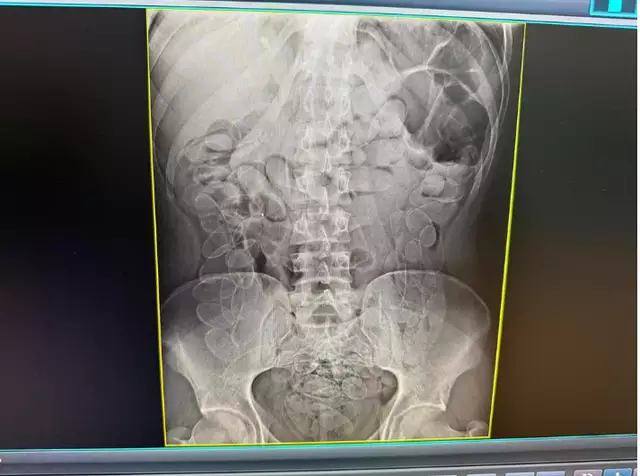

A Polícia Militar foi acionada por volta das 10h para comparecer ao pronto-socorro do município. Segundo a equipe médica, a própria paciente confessou ter ingerido os entorpecentes em território boliviano há cerca de uma semana, permanecendo com o material no organismo durante todo esse período. Um exame de raio-X confirmou a presença de múltiplos invólucros na região abdominal.